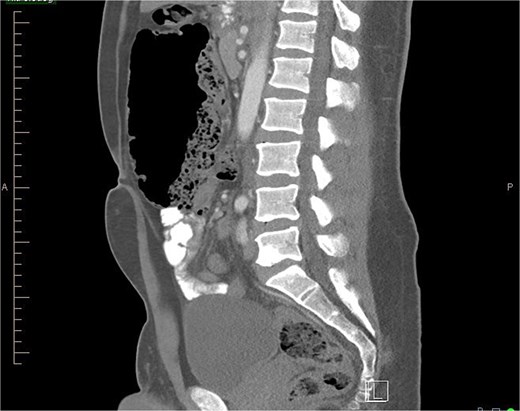

The gold standard for diagnosing malrotation is an upper gastrointestinal (GI) series or a CT scan with oral and intravenous (IV) contrast. In adults, CT is preferred. Characteristic imaging findings include the ‘whirlpool’ sign (Fig. 3a and b), the superior mesenteric vein (SMV) rotation sign, where the SMV lies anterior to the superior mesenteric artery (SMA), as well as right-sided positioning of the bowel, duodenojejunal flexure, and cecum [8] (Fig. 4).

Sagittal view of CT abdomen showing higher and more anterior location of cecum; suggesting a hypermobile cecum (Normally the cecum is located lower in the right lower quadrant).